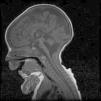

Case 2Male. Uncomplicated delivery at 39 weeks’ gestation, with normal findings in prenatal ultrasound examinations. Apgar score of 8/9. The patient did not need resuscitation in the delivery room. Anthropometric measurements at birth: weight, 2560g (<5th percentile); length, 46.7cm (10th–25th percentile); head circumference, 32.5cm (<5th percentile). The clinical presentation was similar to that of his deceased sister, requiring mechanical ventilation and enteral feeding through a nasogastric tube. The karyotype was 46, XY. Head MRI revealed hypoplasia of the pons and cerebellum, compatible with the diagnosis of PCH type 1 (Fig. 1). The patient died at age 4½ months due to cardiorespiratory failure. The findings of the postmortem histopathological examination (spinal cord and muscle) were consistent with spinal muscular atrophy, with gliosis and a reduced number of Purkinje cells in the granular layer in the cerebellum. Molecular testing detected the same homozygous mutation (c.92G>C) in the EXOSC3 gene, confirming the clinical diagnosis. Both parents were heterozygous carriers of the mutation.